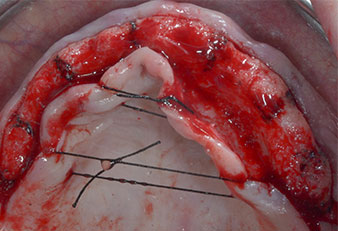

Compte tenu de la dureté relative de l’os (D2) à cet endroit, les sites recevant des implants de 10mm de long aux régions 11 et 21 ont été finalisés à l'aide d’une fraise de 4mm de diamètre, associée à un contre-angle chirurgical W&H WS-75 L, au moteur d'implantologie Implantmed de W&H ainsi qu’au module Osstell ISQ de W&H. En revanche, en raison de leur structure osseuse molle, les sites postérieurs ont été préparés en vue de l’obtention d’un diamètre final de 3mm à l'aide de l’insert Piezomed I3P. Les implants ont enfin été posés par voie transgingivale (Flap Less) pour obtenir l’ostéointégration dans un délai de trois mois (Figures 6-10). L'appareil existant a été maintenu sur quatre implants provisoires (Fig. 8).